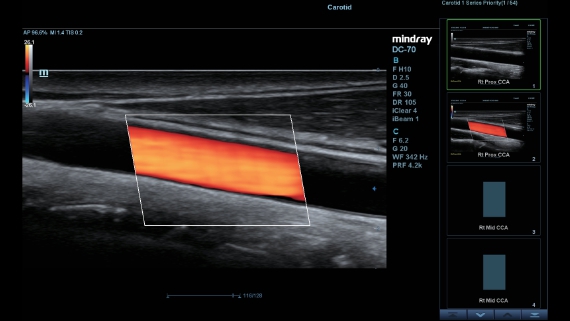

X-Insight ├© una soluzione completa studiata per offrire la migliore qualit├Ā diagnostica.

La nuova soluzione di Mindray ├© la traduzione pratica delle esigenze quotidiane dei clienti in soluzioni cliniche, il tutto con tecnologie ad ultrasuoni all'avanguardia ed in continua evoluzione.

Progettato per rispondere al meglio alle esigenze del cliente, DC-60 Exp con X-Insight ├© studiato per offrire un'efficienza elevata nel campo dell'imaging di precisione, grazie a una chiarezza immediata (eXpress Clarity), allŌĆÖeccezionale intelligenza (eXceptional Intelligence), oltre a vantare una lunghissima esperienza (eXceeding Experience).